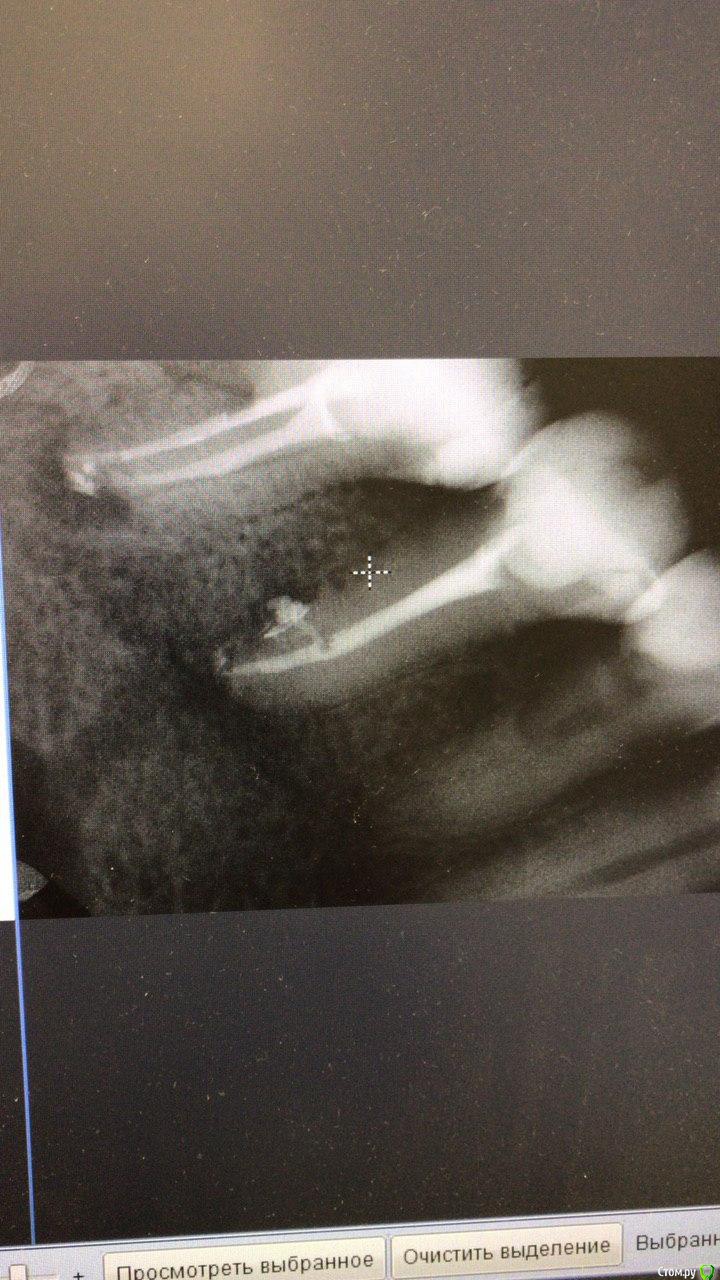

1586Doc Опубликовано 17 мая, 2021 Автор Поделиться Опубликовано 17 мая, 2021 ретрит 46 зуб. Извлечение фрактуры. Дальше будет вкладка и ожидание )) 2 Ссылка на комментарий

Александр23712 Опубликовано 21 сентября, 2021 Поделиться Опубликовано 21 сентября, 2021 (изменено) @1586Doc Фрактура - это трещина. Поэтому "Извлечение фрактуры" немножко режет глаз. *не с целью оскорбить, просто поправка. А работа хорошая. Обработка профайлы? Гидроокись сразу из канюли не страшно вводить? Изменено 21 сентября, 2021 пользователем Александр23712 Ссылка на комментарий

1586Doc Опубликовано 21 сентября, 2021 Автор Поделиться Опубликовано 21 сентября, 2021 10 часов назад, Александр23712 сказал: @1586Doc Фрактура - это трещина. Поэтому "Извлечение фрактуры" немножко режет глаз. *не с целью оскорбить, просто поправка. А работа хорошая. Обработка профайлы? Гидроокись сразу из канюли не страшно вводить? Фрактура - это надлом, перелом)) с немецкого Fraktur — надлом. Обработка профайлы до 30/06. Пару недель гидроокись, потом вертикальная конденсация. Проблем с выводом гидроокиси из канюли никогда не получал. Ссылка на комментарий